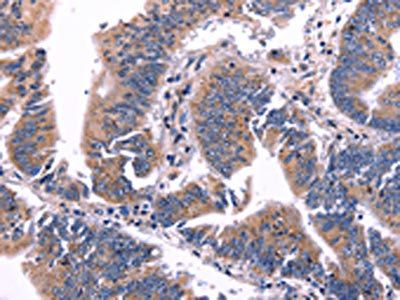

The image on the left is immunohistochemistry of paraffin-embedded Human colon cancer tissue using CSB-PA906268(ARC Antibody) at dilution 1/50, on the right is treated with fusion protein. (Original magnification: ×200)